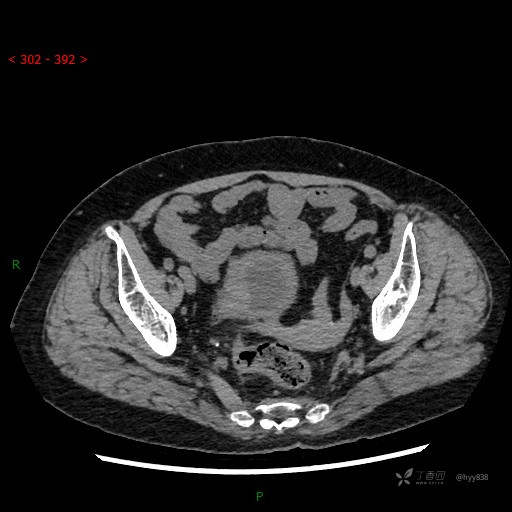

辅助检查:CT

膀胱CT平扫(2022.10.20)

增强(2022.11.1)